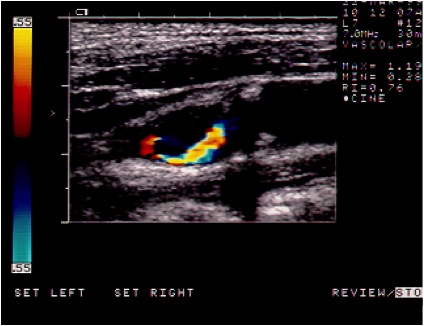

In caso di un restringimento importante delle arterie che portano il sangue al cervello denominate carotidi, in alternativa al tradizionale approccio chirurgico ( TEA o endoarteriectomia carotidea ) in casi selezionati, è possibile intervenire mediante l’introduzione, attraverso un’arteria principale, di un catetere che, posizionato a livello dell’ostruzione, dapprima permette il gonfiaggio di un palloncino che riaprirà il vaso e successivamente consentirà il posizionamento di una speciale maglia metallica ( STENT ) con la funzione di mantenere il vaso aperto nel tempo. Durante la manovra un filtro, posizionato a monte della stenosi, avrà il compito di bloccare e trattenere eventuali impurità che si dovessero generare nel corso della procedura stessa.